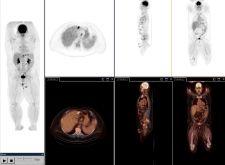

With a growing focus on cardiology applications, GE Healthcare strives to enhance image quality through dynamic, gated PET and volumetric CT. The company introduced at the end of 2005 the Discovery VCT, a system that aims to convey a clearer view of the heart. The system combines PET’s dynamic and gating data, acquiring a comprehensive view of the heart and coronary arteries with submillimeter resolution in five seconds, with volumetric CT used to visualize the anatomy of the heart’s blood vessels. The VCT also features VUEPoint reconstruction, offering fully iterative reconstruction technology in 2-D and 3-D acquisition modes.

The angle that Siemens has carved out for improving PET/CT images is focusing on increased count rates. Siemens has adopted this approach by introducing TruePoint technology into its Biograph system. Designed for nuclear medicine applications where clinicians require extremely precise and detailed images to pinpoint minute lesions and arteries, True Point reportedly adds 33 percent more axial volume coverage to its PET/CT scanner, extending the field of view and improving counts by more than 78 percent.

Hitachi’s SceptreP3 employs Dual Attenuation Correction (DAC) technology, which allows the combination of both CT and sealed source attenuation correction to effectively image patients with metal implants. In addition, the Non-Rigid Fusion 7-D algorithm provides precise registration by correcting for respiration differences between PET and CT acquisitions.